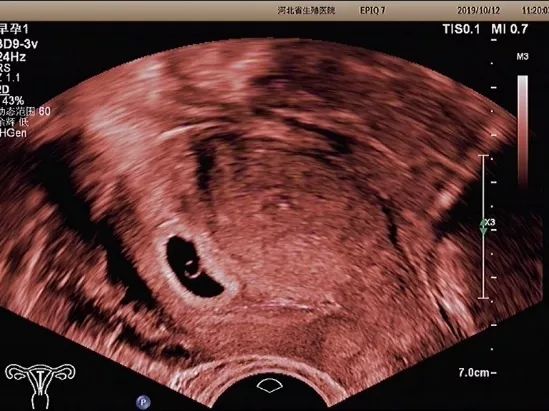

孕早期超声检查的内容

孕早期超声检查的内容主要有

以下5个方面

妊娠囊

确定妊娠囊是否在宫腔内,妊娠囊在宫腔内的位置、数目及大小。妊娠囊的大小可随孕周增长而增长。

卵黄囊

卵黄囊是妊娠囊内超声能发现的第一个解剖结构。当超声发现卵黄囊,即可以确定妊娠。正常的卵黄囊直径约3~8mm,卵黄囊过大、过小或不显示及变形均提示妊娠结局不良。

胚芽

可根据胚芽长度评估孕周,有无心管搏动,确定胚胎是否存活。

经阴道超声检查

经阴道超声检

查又称腔内超声

经阴道超声有哪些优势呢?

优势一

经阴道超声检查发现

妊娠囊、卵黄囊的时间

早于经腹部超声

常能发现经腹部超声

不能发现的宫内早早孕和异位妊娠